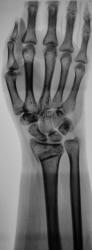

У пациентки снят ГИПС. Пациентка направлена на рентгенографию лучезапястного сустава с целью рентгенологического подтверждения консолидации.

Настораживает повышенная плотность отдельно лежащего фрагмента по передней поверхности метафиза луча на фоне  легкой общей минералопении, признаков формирования костной мозоли не видно - есть основания зподозрить нарушение его трофики с последующим формированием секвестра.

Консолидации нет.